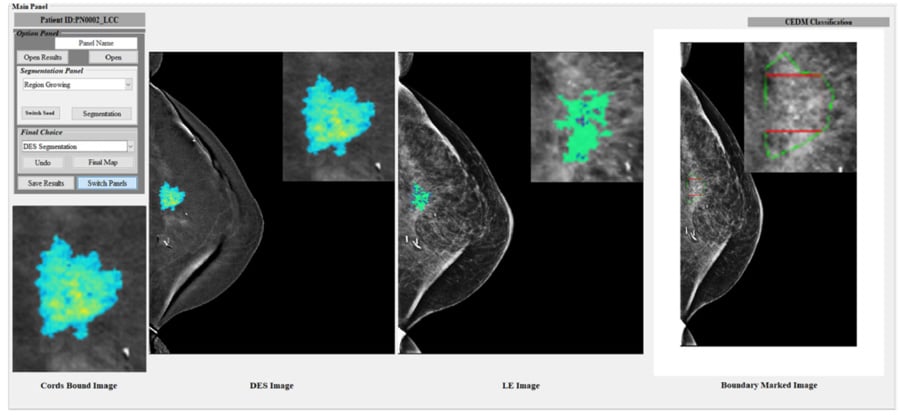

近年来,对比增强数字乳房x线照片(CEDM)已成为一种很有前景的新成像方式。该技术利用了DDDM提供的高空间分辨率和乳腺磁共振成像(MRI)提供的生理功能信息,具有显著的快速扫描和低成本。然而,开发CEDM的CAD方案来帮助放射科医生更准确地诊断可疑病变的可能性还没有被研究过。

郑教授及其在市长庭院亚利桑那州和亚利桑那州立大学的合作者一直致力于开发新的CEDM的CAD计划。ABME文件中报告的工作[9]呈现了第一个全自动CEDM的CEDM,以分类恶性和良性乳腺病变。研究结果表明,如果提高病变,则来自双能量减法(DES)图像的病变的分割更容易更具准确性,更准确。其次,除了最终可能是缺点的DES丧失的病变密度异质性信息,CAD通过将DES图像到低能量FFDM图像绘制更好的病变分段结果来产生显着提高的性能。如果在未来的大规模研究中可以进一步验证结果,使用CEDM和CAD将在减少未来乳腺癌诊断中减少不必要的活组织检查方面发挥重要作用。